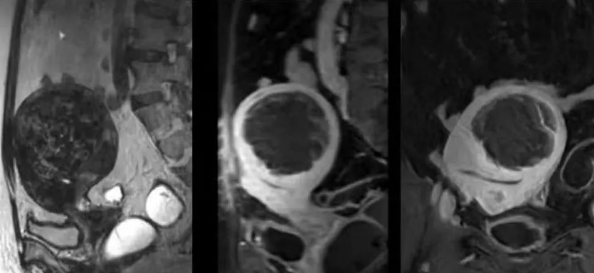

陳寶瑩主任首先給祝女士進(jìn)行了詳細(xì)的盆腔磁共振評(píng)估,發(fā)現(xiàn)子宮肌瘤比較大,直徑七公分,類(lèi)型和位置都適合做磁波刀治療。陳寶瑩主任立即為她制定了個(gè)性化治療方案,并為她完成幾項(xiàng)術(shù)前檢查。

治療當(dāng)天,為緩解祝女士的緊張心情,陳寶瑩主任和她進(jìn)行了充分溝通。術(shù)前準(zhǔn)備就緒后,治療正式開(kāi)始了。治療過(guò)程中,患者全程清醒,可以及時(shí)反饋治療感受。醫(yī)生也即時(shí)調(diào)整,確保整個(gè)治療安全有效,兩小時(shí)后治療順利結(jié)束,患者體驗(yàn)度好。即時(shí)評(píng)估發(fā)現(xiàn)7公分的子宮肌瘤被消融掉80%,達(dá)到了預(yù)期目標(biāo)。祝女士觀察一個(gè)小時(shí)后,沒(méi)有什么不舒服即回家了。